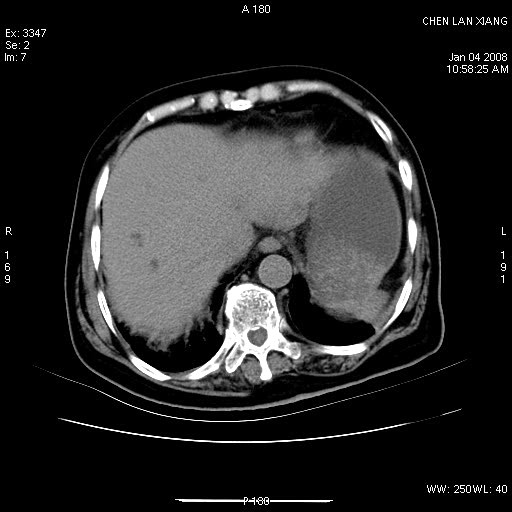

女,76岁,腹痛3-4天,b超示:肝内实性肿物,胆囊强回声,胆总管扩张.

1 胆总管末端结石伴肝内胆管结石,肝内外胆管扩张。2 胆囊扩大,胆囊壁不规则增厚,内见软组织密度影。考虑:慢性胆囊炎,不除外胆囊癌!

胆囊密度增高,增强后周边肝组织及胆囊窝下部周边软组织延时性不规则强化.然胆囊壁未见明显不规则增厚及肿块.左侧肝内胆管及胆总管下段结石伴胆系扩张.

考虑;胆囊炎(黄色肉芽肿性胆囊炎?),左侧肝内胆管及胆总管下段结石.

ct所见:1、 肝内胆管结石,肝内外胆管扩张。低位胆道梗阻,胆总管下端结石;2 胆囊扩大,胆囊壁不规则增厚

考虑:胆总管下端结石并肝内外胆管扩张,肝内胆管结石;

1)胆囊癌伴肝脏转移。2)胆总管下端结石、肝内胆管结石伴肝内外胆管扩张。